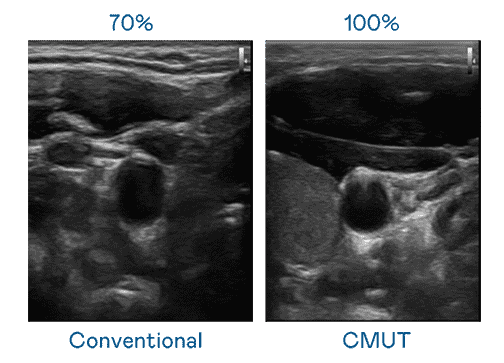

CMUT 技术是一种用电容式微机电元件来产生超音波讯号的技术。。与传统 PZT 压电式技术相比,,,CMUT 频宽增加 30%,,,,更宽频的超音波讯号让影像解析度大幅提升,,,是实现高影像品质医疗超音波扫描、、、、促进精准医疗发展的关键技术。。。。

超音波影像的解析度高低,,,,首先取决于探头能发出的讯号频宽。。。。彩神vll CMUT 可提供高清晰的超音波讯号,,,提供高频宽、、、高灵敏度、、、、影像纹理细节更高的超音波影像,,协助医护人员缩短影像判读时间及利用精准的医疗影像进行诊断。。。。